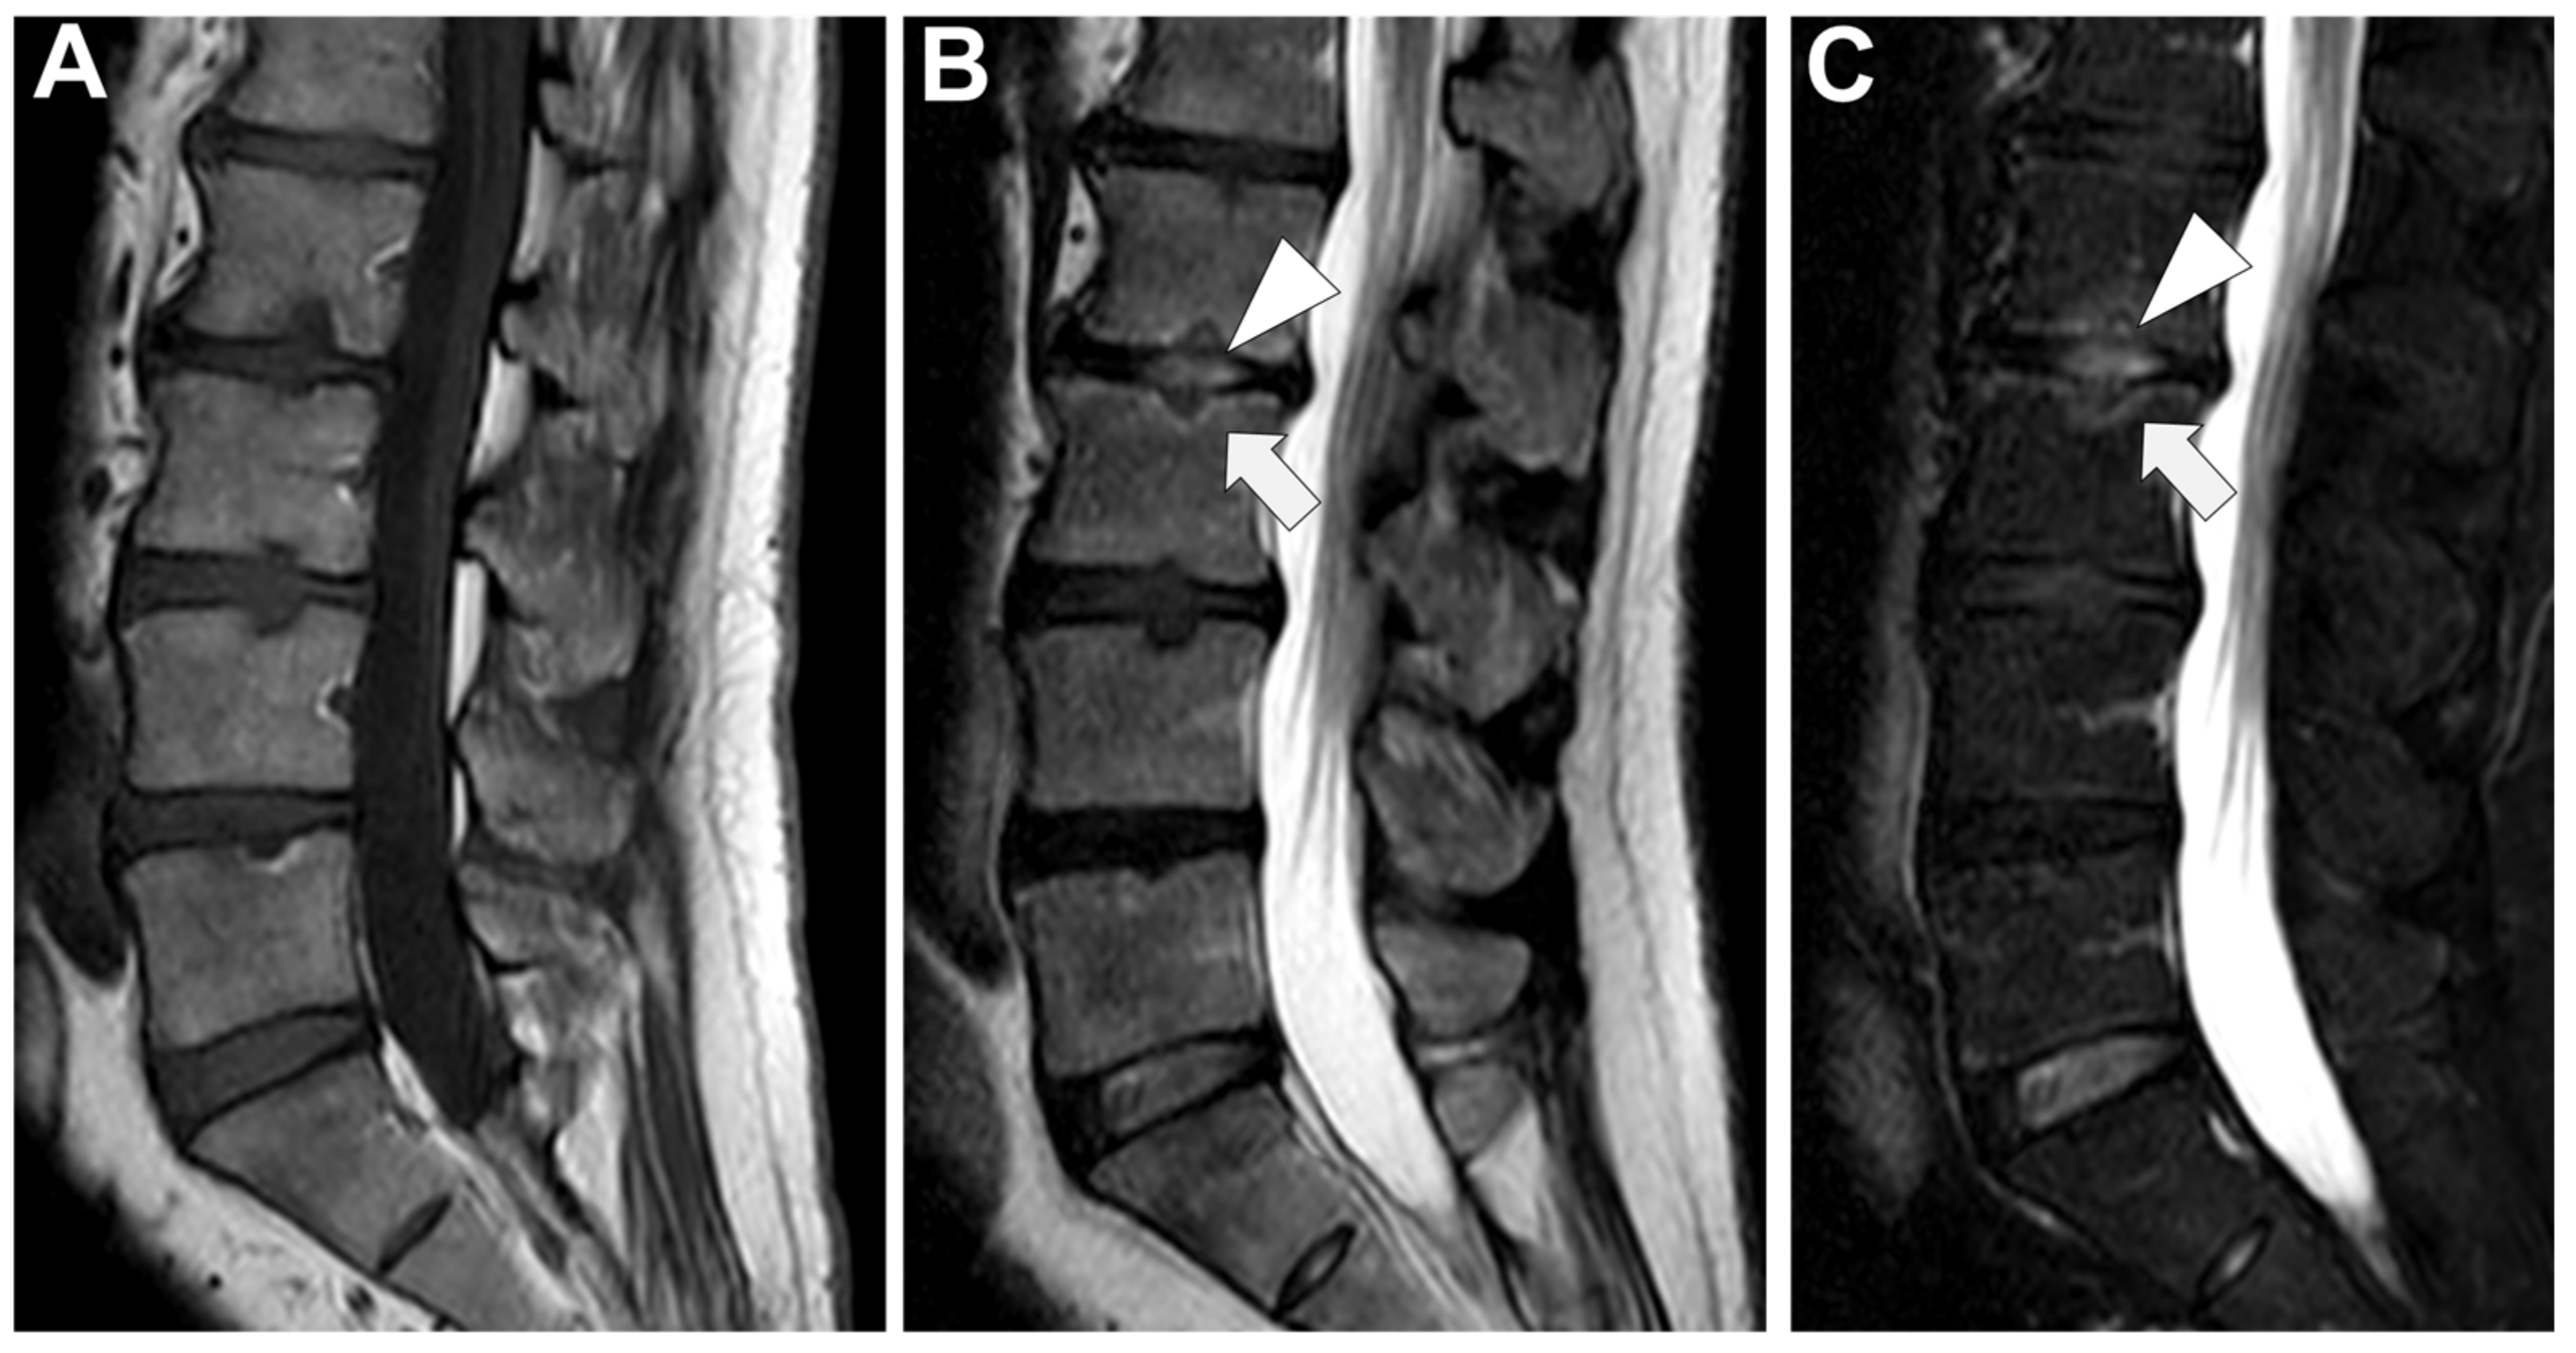

Figure 7. A 73-year-old male presented with a rapidly evolving lumbar pain and fever, with an inflammatory syndrome on blood samples. A first MRI was performed as infectious spondylodiscitis was suspected, which included (A) STIR T2-weighted imaging (WI) and (B) fat sat T1-WI after gadolinium chelates injection. It shows a high signal intensity (SI) of the L3-L4 disc while other disks are in lower signal (black arrowhead), as well as linear subchondral contrast enhancement (CE) of the L3-L4 endplates both linear and more pronounced at the upper anterior corner of the L4 vertebral body (white arrowheads). Moreover, the left T11-T12 facet joints displayed marked edema of the subchondral bone and surrounding tissues (white arrows). A control MRI with SITR T2-WI (C) and fat-suppressed CE-T1-WI (D) was performed one month later, demonstrating a marked narrowing of the L3-L4 disk (black arrowhead), erosions of the vertebral body (dashed white arrows), extensive edema in the L3 and L4 vertebral body (white arrowhead), a persisting arthritis involving the left T1-T12 facet joint. Bacillus cereus was found on the Bacterial analysis of the L3-L4 disk biopsy.